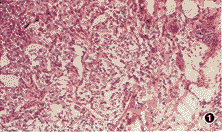

病理检查:结节状软组织标本2.5 cm×2.5 cm×2.0 cm大小,切面均质、褐色,无明显包膜。镜下观察:瘤细胞呈巢状及条索状分布,多边形,大小较一致,未见核分裂象,肿瘤间质富含毛细血管(图1)。嗜铬染色阳性。免疫组化:嗜铬粒A强阳性(图2)。

图1 膀胱嗜铬细胞瘤 HE×100 图2 示瘤细胞嗜铬粒A免疫组化染

色呈阳性 SP法×400